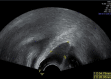

Figure 3

Longitudinal ultrasonographic image using high frequency transvaginal transducer (5–12 MHz), showing a well-defined hypoechoic elongated cyst with 5.5 cm of long axis with septations.